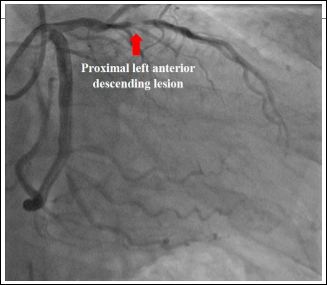

Our second case was a 67-year-old male with no prior cardiac history who presented with an acute anterior STEMI. Emergency coronary angiography revealed a single coronary artery with a critical stenosis in the proximal LAD (culprit lesion) and RCA arising from the distal circumflex artery (Figure 2). Successful primary PCI of proximal LAD was performed (Figures 3 & 4). Echocardiography was done during admission showing no associated structural heart disease. Patient was discharged after 4 days of hospital stay without any complications and remained asymptomatic during follow up.

Figure 3: Proximal Left Anterior Descending (pLAD) lesion before percutaneous coronary intervention.